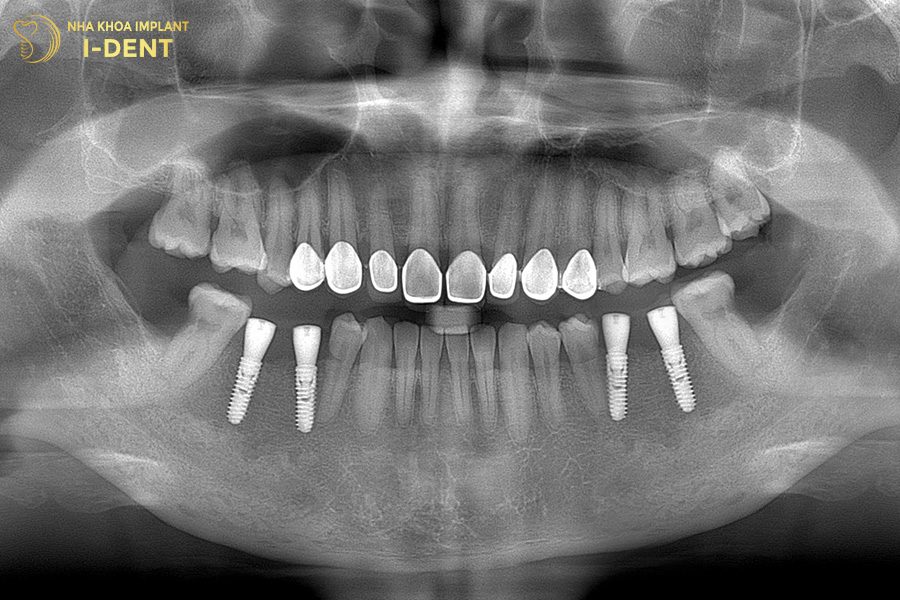

Tình trạng răng ban đầu của chú Trương Văn Sự

Nhận định đây là một tình trạng bệnh khá phức tạp, bác sĩ Đình Tín đã thăm khám kỹ lưỡng và đưa ra kế hoạch điều trị chi tiết. Đầu tiên, bác sĩ Tín chỉ định nhổ các răng lung lay, phẫu thuật ghép xương lớn tại những vị trí tiêu xương, sau đó mới tiến hành cấy ghép Implant toàn hàm All-on-4 cho chú Sự. Cuối cùng là phục hình toàn hàm với răng sứ Chrom-Cobalt (Mỹ) trên Implant cho chú.

Hình ảnh răng chú Sự sau khi cấy ghép Implant All on 4 cho hàm trên